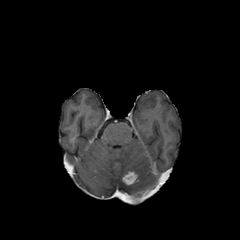

Objectives: This work aims to explore the impact of multicenter data heterogeneity on deep learning brain metastases (BM) autosegmentation performance, and assess the efficacy of an incremental transfer learning technique, namely learning without forgetting (LWF), to improve model generalizability without sharing raw data. Materials and methods: A total of six BM datasets from University Hospital Erlangen (UKER), University Hospital Zurich (USZ), Stanford, UCSF, NYU and BraTS Challenge 2023 on BM segmentation were used for this evaluation. First, the multicenter performance of a convolutional neural network (DeepMedic) for BM autosegmentation was established for exclusive single-center training and for training on pooled data, respectively. Subsequently bilateral collaboration was evaluated, where a UKER pretrained model is shared to another center for further training using transfer learning (TL) either with or without LWF. Results: For single-center training, average F1 scores of BM detection range from 0.625 (NYU) to 0.876 (UKER) on respective single-center test data. Mixed multicenter training notably improves F1 scores at Stanford and NYU, with negligible improvement at other centers. When the UKER pretrained model is applied to USZ, LWF achieves a higher average F1 score (0.839) than naive TL (0.570) and single-center training (0.688) on combined UKER and USZ test data. Naive TL improves sensitivity and contouring accuracy, but compromises precision. Conversely, LWF demonstrates commendable sensitivity, precision and contouring accuracy. When applied to Stanford, similar performance was observed. Conclusion: Data heterogeneity results in varying performance in BM autosegmentation, posing challenges to model generalizability. LWF is a promising approach to peer-to-peer privacy-preserving model training.